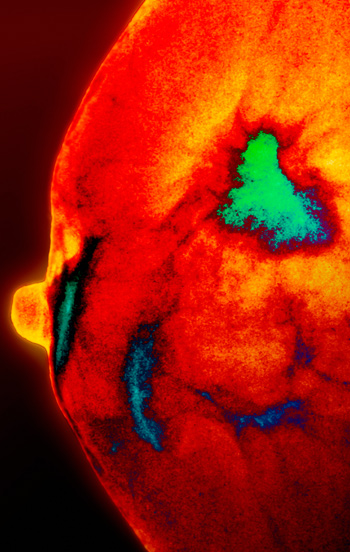

Kolesterolmetabolitten 27-hydroksykolesterol fremmer østrogenreseptoravhengig vekst av humane brystkreftceller.

Høyt kolesterolnivå gir økt risiko for å få østrogenreseptorpositiv brystkreft og er assosiert med dårligere respons på hormonbehandling. To uavhengige forskergrupper har nylig undersøkt effekten av kolesterolmetabolitten 27-hydroksykolesterol på brystkreft (1, 2).

Forskerne viste at både en kultivert human brystkreftcellelinje, MCF7, og humane brystkreftceller implantert i en musemodell vokste raskere i nærvær av 27-hydroksykolesterol. Kolesterolmetabolitten førte også til raskere spredning av svulsten til andre organer. Undersøkelse av humane brystkreftsvulster viste at de mest aggressive kreftsvulstene inneholdt høyere nivåer av enzymet CYP27A1 (som omdanner kolesterol til 27-hydroksykolesterol) enn de mindre aggressive.